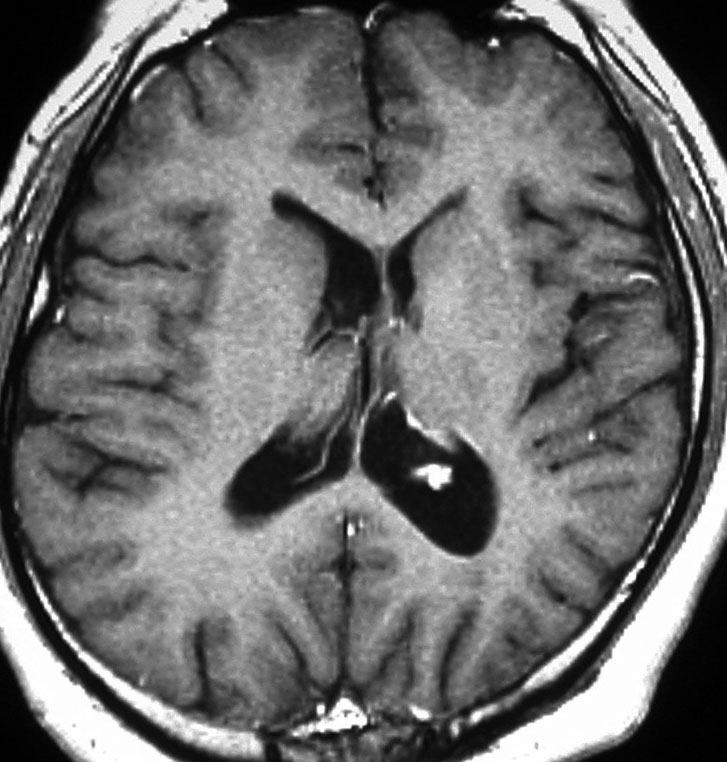

脳MRI 3.血管障害・腫瘍・感染症・他 | 高橋昭喜, 高橋昭喜 |本 | 通販。感染性心内膜炎と中枢神経合併症│医學事始 いがくことはじめ。転移性脳腫瘍とは?症状・診断・治療法を脳神経外科専門医が徹底解説。本棚にしまっていましたが使用しないので出品します。書き込みありません。非裁断です。「脳MRI 3 血管障害・腫瘍・感染症・他」高橋 昭喜定価: ¥ 12000#高橋昭喜 #高橋_昭喜 #本 #自然/医療・薬学・健康。脳腫瘍 | 脳神経外科の主な疾患と治療方法 | 江戸川病院。。★金原出版★カラーフォト皮膚病★籏野 倫★1〜4巻★国立国会図書館所蔵★お店の情報